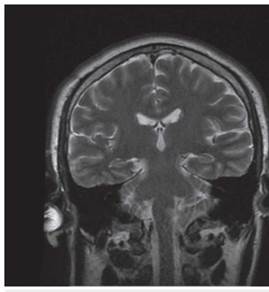

<p>Los estudios de hemograma, nitrógeno ureico, creatinina, glucemia y electrolitos se encontraron dentro de los rangos normales, el perfil lipídico mostró: colesterol total 160 mg/dl, colesterol HDL 50 mg/dl, colesterol LDL 89,8 mg/dl, triglicéridos 101 mg/dl. La tomografia de cráneo simple no mostró sangrado ni signos de isquemia. Se realizó una resonancia magnética cerebral simple que permitió evidenciar en las secuencias de T2 y FLAIR <italic>(Fluid Attenuation Inversion Recovery)</italic> una zona de hiperintensidad de señal a nivel del bulbo raquídeo en la región dorso-lateral caudal izquierda que es hipointensa en T1 (<xref ref-type="fig" rid="f1">figuras 1</xref>,<xref ref-type="fig" rid="f2">2</xref>,<xref ref-type="fig" rid="f3">3</xref>,<xref ref-type="fig" rid="f4">4</xref>). En la secuencia de difusión se observa restricción de la misma en la zona descrita con fenómeno de pseudonormalización al igual que en el mapa ADC <italic>(Apparent Coefficient Diffusion}</italic> (<xref ref-type="fig" rid="f5">figuras 5</xref>,<xref ref-type="fig" rid="f6">6</xref>). Los anteriores hallazgos se interpretaron como compatibles con un infarto bulbar lateral izquierdo.</p>

<p>El paciente se caracterizó por tener principalmente dis-fagia, disfonía, vértigo, ataxia y hemiparesia ipsilateral, las cuales rápidamente mejoraron, siendo llamativo la ausencia de nistagmo el cual se reporta en una incidencia importante. El estudio por resonancia magnética se logró realizar 1 semana posterior al inicio de los síntomas, lo cual generó la limitante de observar pseudo-normalización en la secuencia DWI (Diffusion Weighted Imaging) y por ende ausencia de una clara restricción de la difusión. En el T2 corte coronal se puede ver extensión hacia zonas caudales de la unión bul-bomedular, lo cual explicaría por qué presentó compromiso del tracto cortico-espinal siendo la primera causa, la lesión de las fibras ya decusadas provenientes del hemisferio contrala-teral ya sea por isquemia o por efecto de masa por el edema adyacente, este hallazgo se correlaciona con lo mayormente reportado en otras publicaciones. Un elemento importante en el paciente fue el inicio súbito de los síntomas posterior a realizar una rotación brusca del cuello con dolor cervical asociado, lo cual debe ubicar al clínico en un contexto cuya principal etiología a estudiar sea la disección cervical dada además la ausencia de factores de riesgo cardiovasculares y la edad cercana a los 50 años, sin embargo, en una angiografía convencional tomada 3 semanas después, no se evidenció esta etiología según lo informado por radiología. A pesar del compromiso motor, no todos los pacientes que cursan con síndrome de Opalski tienen una afectación marcada de la funcionalidad e independencia <xref ref-type="bibr" rid="B17"><sup>17</sup></xref> y la debilidad evidenciada es leve y transitoria permitiendo su recuperación hasta el 100 % previo, como se observó en este caso. Por otro lado, es importante evitar complicaciones tempranas como la broncoaspiración y neumonitis secundaria y, por ende, se hace imperativo plantear desde el ingreso de estos pacientes una vía alterna de alimentación a través de sonda naso u orogástrica o gastrostomía mientras se lleva a cabo el proceso de rehabilitación de la disfagia de forma paralela.</p>